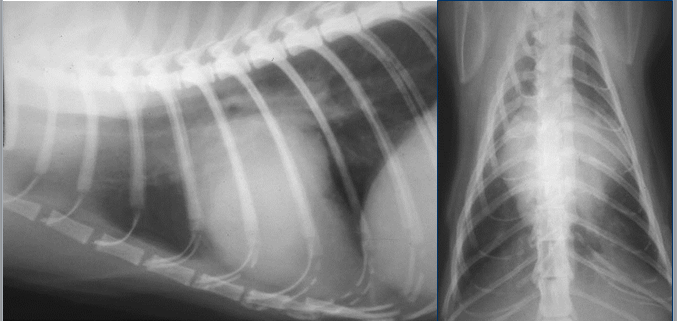

What can be seen here?

Caudal mediastinum

Blue – aorta

Yellow – vena cava

Don’t normally see normal oesophagus on radiograph

Reflection of pleura – represents the left part of caudal mediastinum – its not actually in midline, its slightly over to the left – if increased opacity in this caudal mediastinum, this is where increase will be – if its more midline opacity, more likely to be right lung lobe.